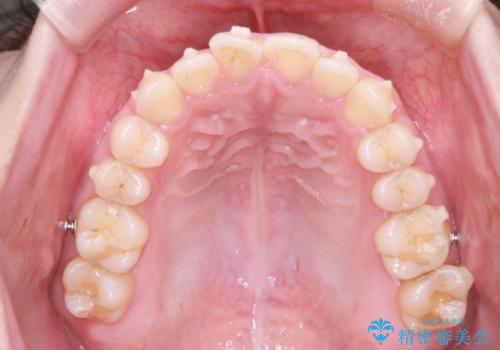

- 笑った時の前歯の見た目が気になることを主訴に来院されました。

上の歯が下の前歯を少し隠すぐらいを目指し、インビザラインにて治療を行いました。

オープンバイトの後戻りを防ぐためには舌のトレーニングが必要です。